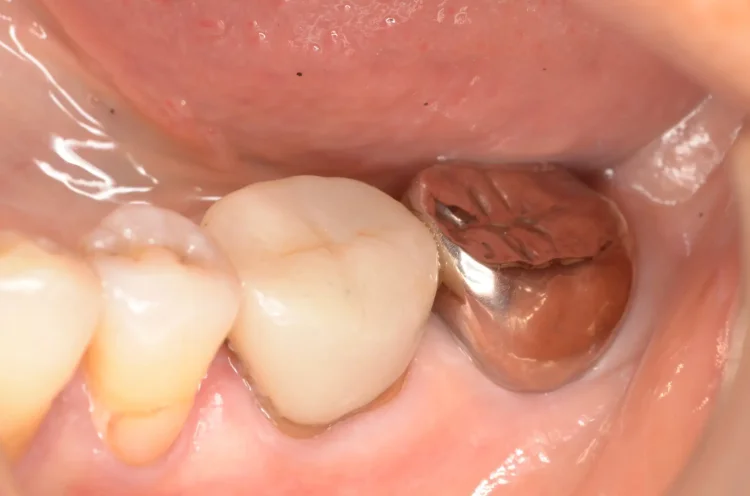

Before

After

インプラント周囲炎に対応(80代女性)

2ヶ月 / 総額40,000円リスク・副作用:インプラント周囲炎はご自分の歯の歯周病と同じで、一度落ち着いてもケアを怠ると再発してしまいます。 いい状態を維持できるように、しっかりメンテナンスが必要です。